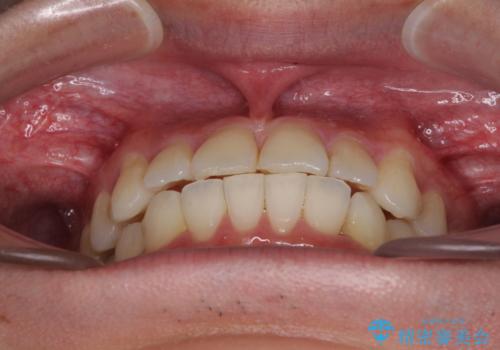

- 30代男性

- 矯正装置

- 審美装置

- 治療期間

- 1年2ヶ月

- 右下奥歯の虫歯がしみて痛いとのことで来院された患者様です。

神経近くにまで及ぶ大きな虫歯でしたが、速やかに処置を行い、痛みは即日解消されました。

虫歯が大きかったため、クラウンによる補綴治療が必要になる旨をお伝えしたところ、矯正治療にも興味があるとのことでした。

短期間で手間のかからない方法がご希望でしたので、ワイヤー装置による矯正治療を行うこととし、矯正治療後に右奥2歯をセラミッククラウンにて補綴することとしました。